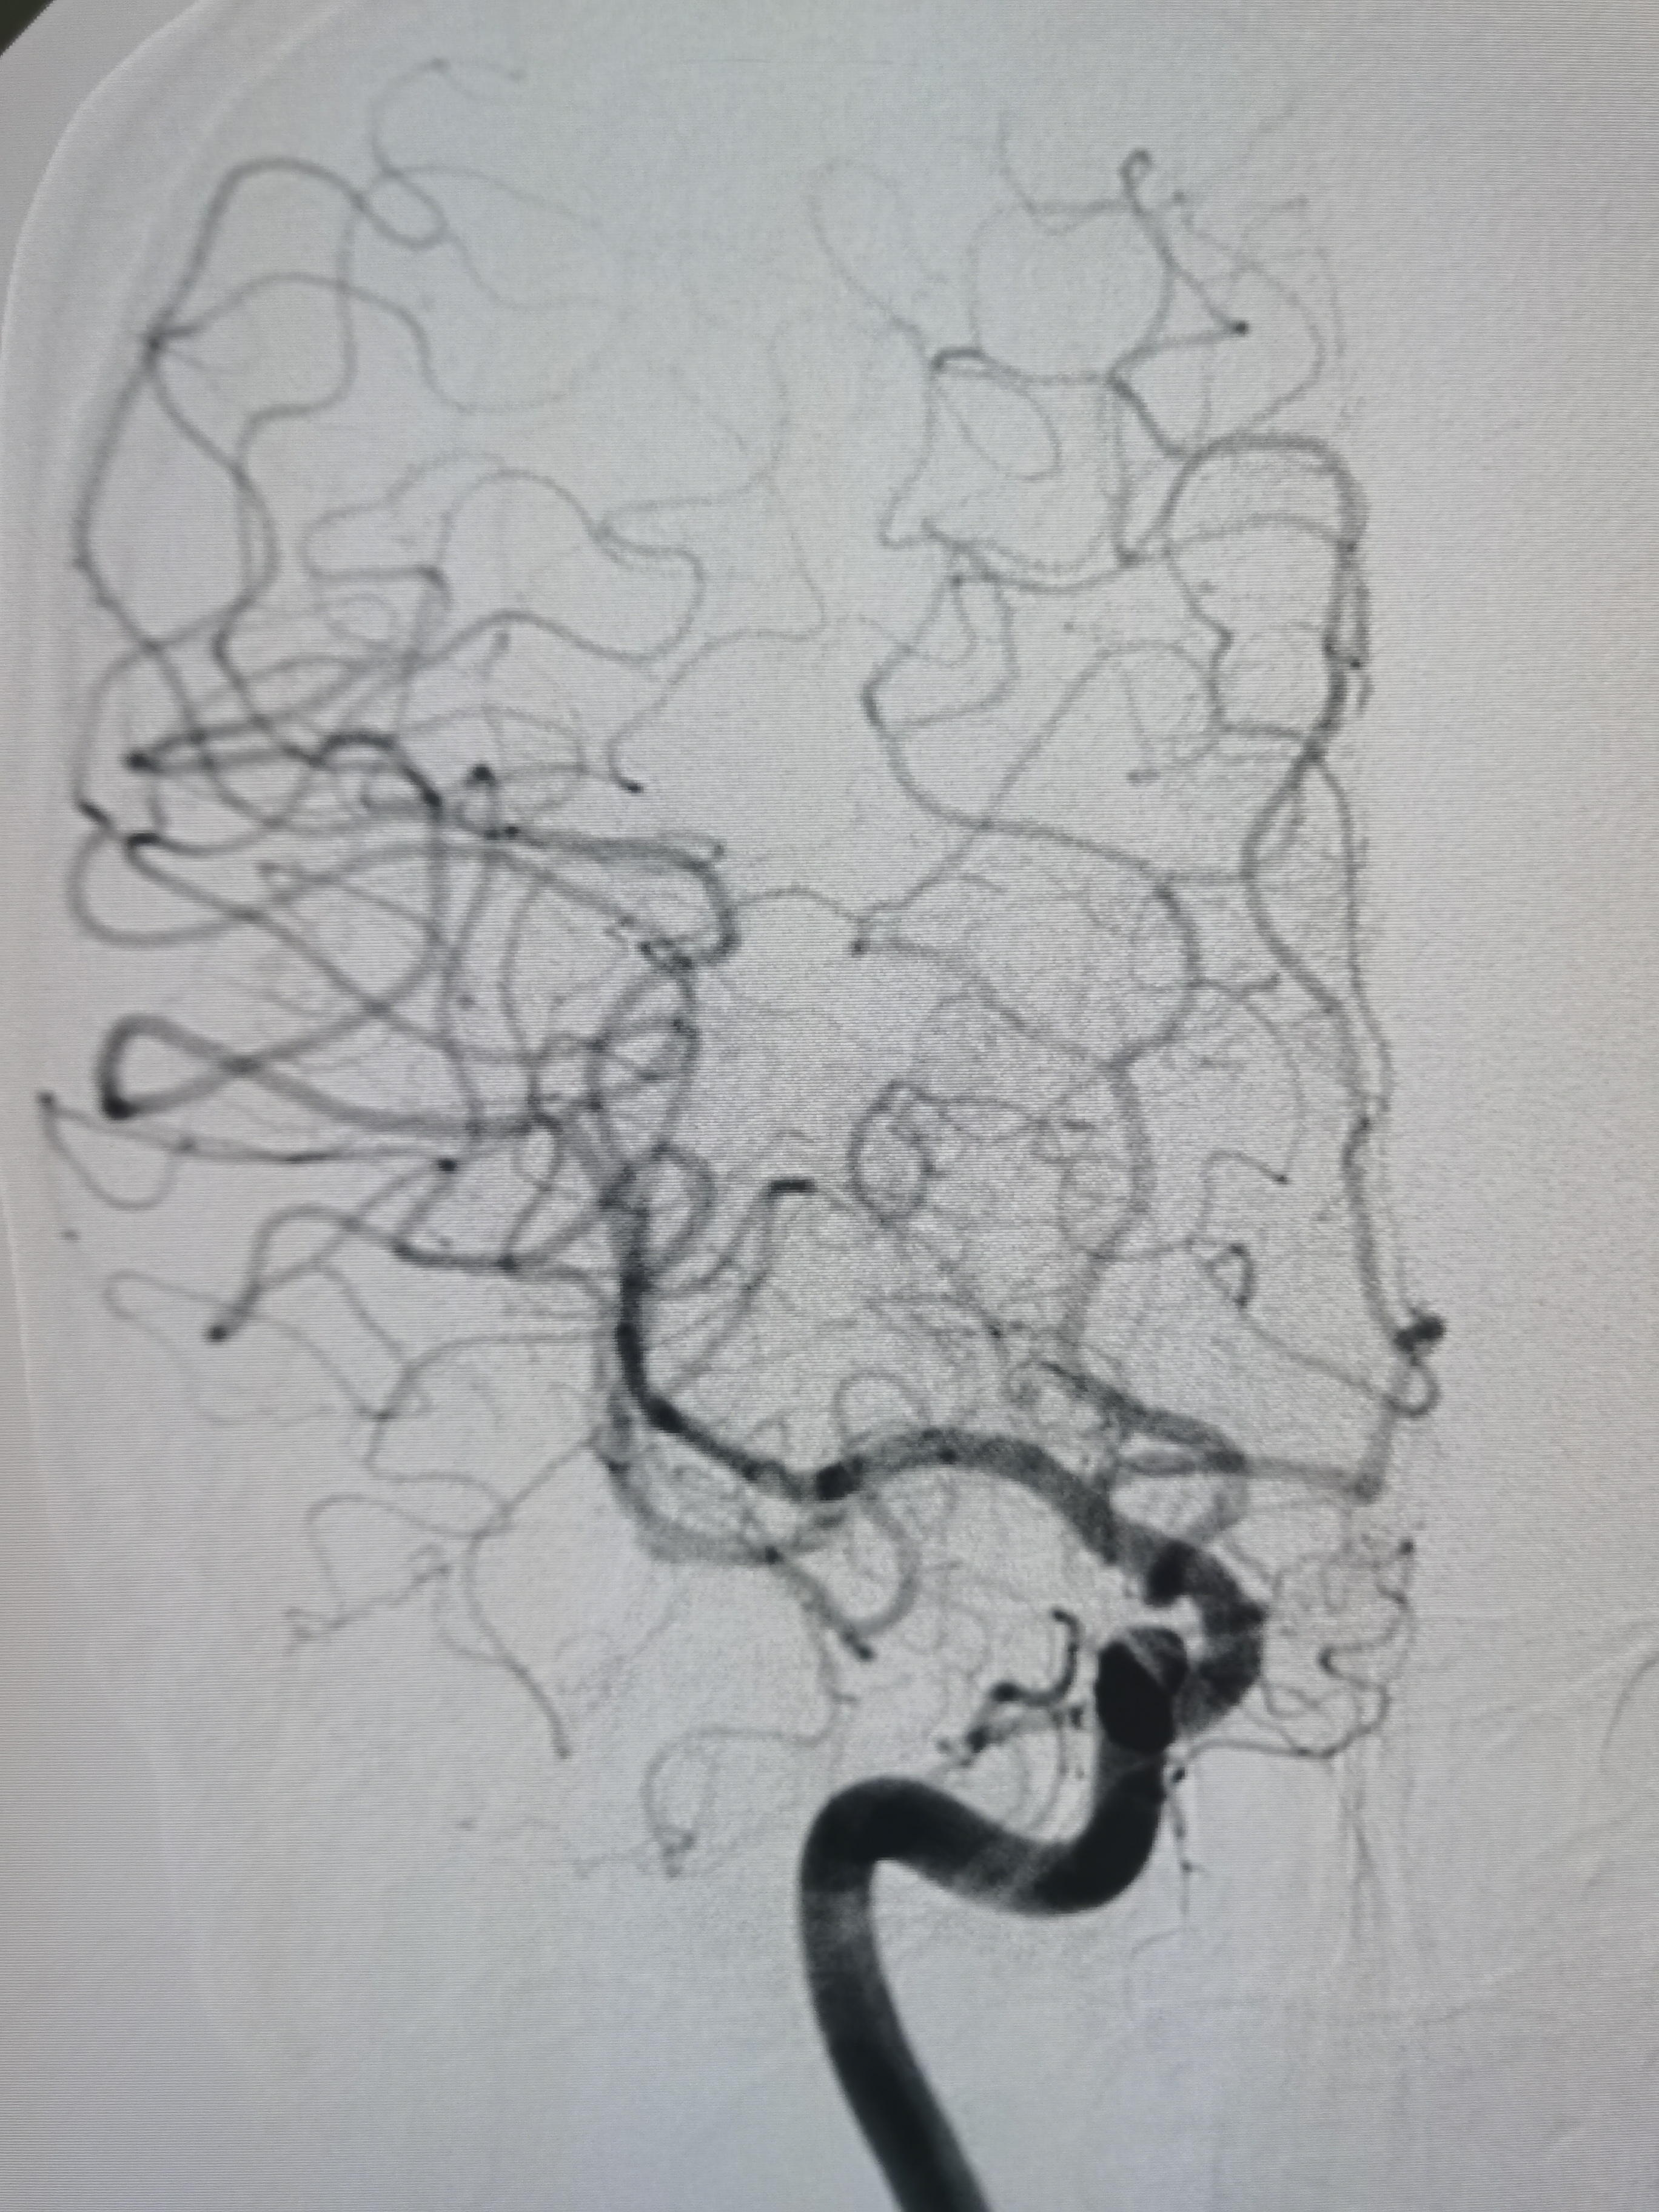

取栓后颅内血管再通,血流通畅。

术前术后对比。